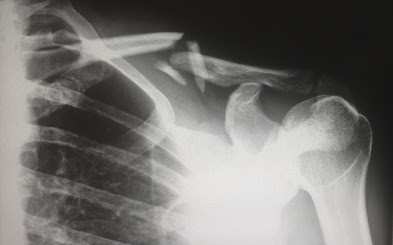

Through physical examination techniques and imaging tests such as X-rays and MRI scans, doctors can accurately diagnose rotator cuff tears to get a detailed view of the affected soft tissues.

• X-ray: Reveals bone-related issues that might contribute to symptoms.